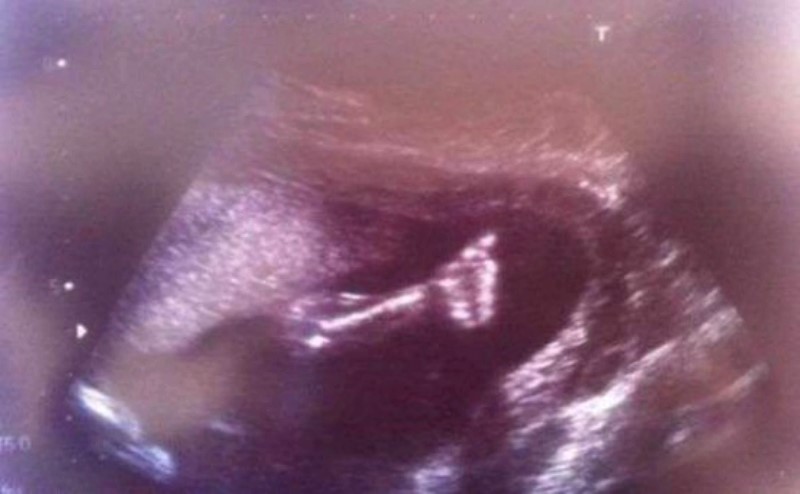

Энэ зураг дээрх охиныг төрөлхийн зүрхний хүнд гажигтай, амьдрах магадлал бараг 0-тэй тэнцүү гээд хоёр ч удаа үр хөндөлт хийхийг эмч нар эцэг, эхэд нь санал болгож байжээ.

Гэтэл эцэг эх нь эхо-д хартал охин бүх юм сайн гэсэн шиг эрхий хуруугаа гозойлгосон байхыг харсан эцэг эх нь охины амьдралын төлөө эцсээ хүртэл тэмцэхээр болсон байна. Ингэснээр Шанель гэдэг нэр авсан энэ охины төрөөд ердөө дөчин минутын дараа зүрхний хүнд хагалгаанд орж, долоо хоногийн дараа дахин хагалгаанд ороод эсэн мэнд бойжиж байна. Үүнийг жинхэнэ гайхамшиг гэхгүй өөр юуг гайхамшиг гэх билээ.